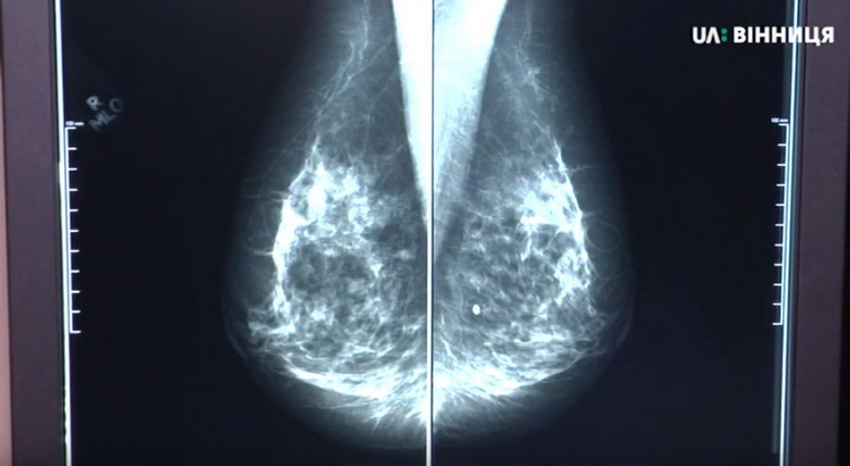

Лікар Ігор Іванов каже, що УЗД молочних залоз треба робити двічі на рік з 18 років. Додає, що більшість жінок нехтують власним здоров’ям. А після 40-ка років робити УЗД молочних залоз потрібно в комплексі з мамографією.

«Злоякісна пухлина – це утворення, яке жінка, можливо, не пальпувала в себе сама. Воно виявилося лише під час обстеження. Не деформувало грудь, не давало візуальної деформації. Лише дало початкові прояви – дрібні кальцинати – 100% прояв злоякісної пухлини.